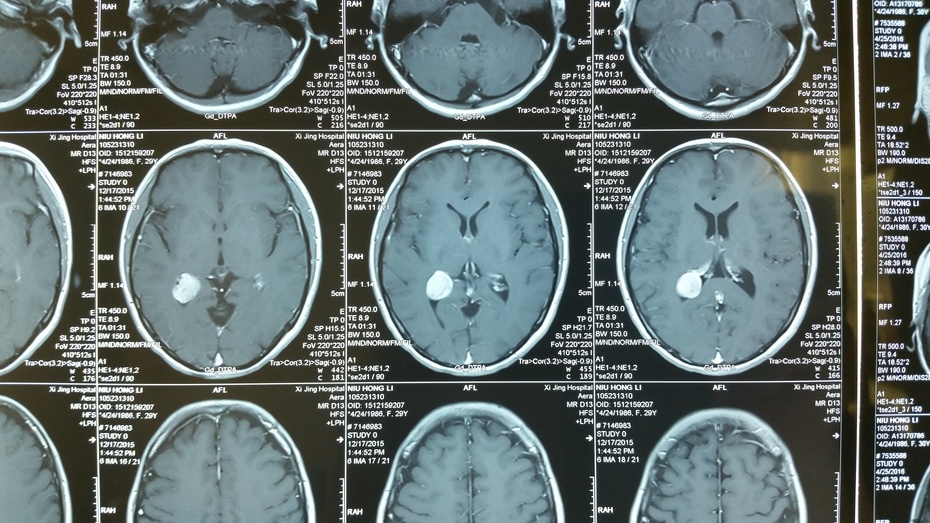

图一:头部ct扫描显示:侧脑室内巨大肿瘤,梗阻性脑积水河南的男性患者

图片尺寸558x671